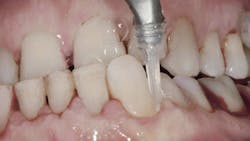

Air polishing accesses challenging areas more efficiently1,7 (figure 1) and reduces biofilm levels in periodontal pockets significantly more than hand-activated instrumentation.1,4,6 The PWR Pair offers the advantage of two powders:

- Sodium bicarbonate powder for the removal of heavier stain supragingivally Glycine powder for supra/subgingival access with a standard nozzle that reaches PD up to 4 mm and subgingival nozzle for PD up to 5 mm.1 A flexible narrow tip is attached to the subgingival nozzle to allow for subgingival access with minimal tissue distention (figure 2).1,3,6